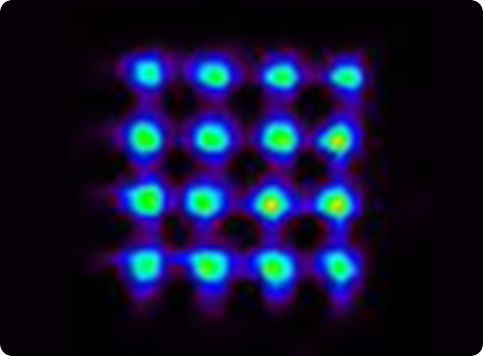

Figure 9

Set of point sources without DOI measurement (5 mm separation).

Figure 10

Set of point sources with DOI measurement (5 mm separation).